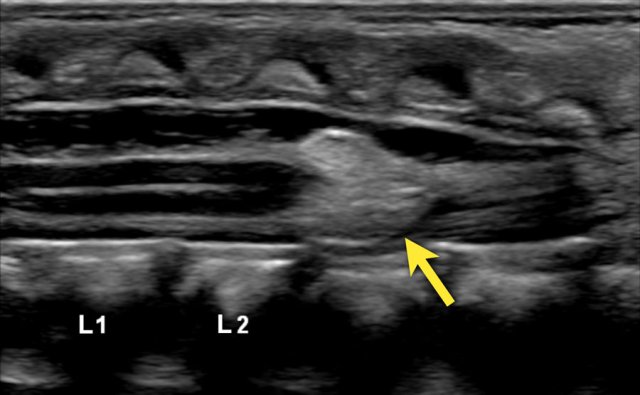

This was a newborn boy with an anorectal malformation.

An ultrasound was performed to look for signs of occult spinal dysraphism.

There is a thickened filum with a low ending conus medullaris at L3-L4 and a mild hydromyelia.

Continue with the sagittal video.

On the sagittal video the low ending conus medullaris is seen at L3-L4.

The upper limit of normal for the width of the filum terminale is 2 mm.

If it is thickened it often shows fatty infiltration with hyperechoic tissue.

In healthy newborns, the tip of the conus medullaris is located between L1 and L2.

The tip should not be positioned below L2-3.